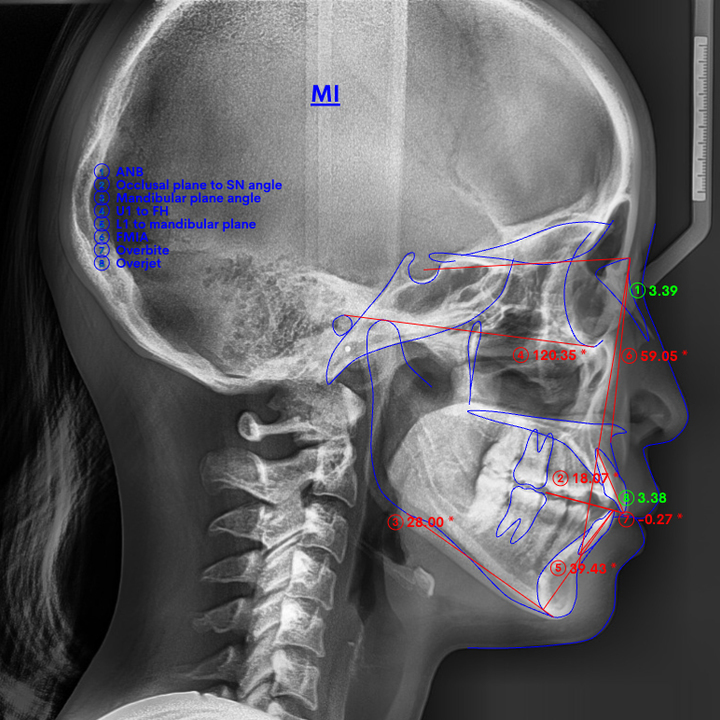

精密検査

治療計画